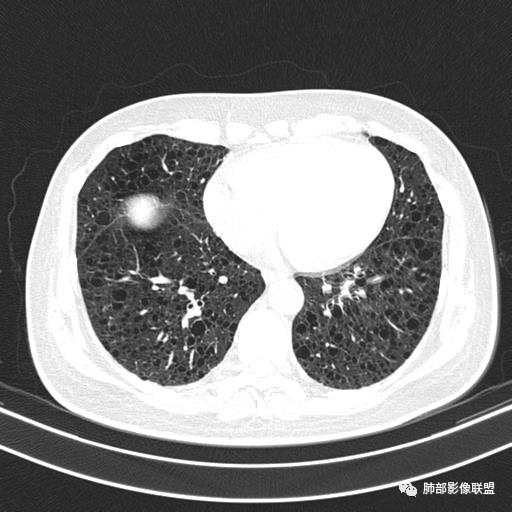

中年女性,不吸烟

双肺弥漫囊腔,累及肋膈角,囊腔形态相对规则单一。

符合LAM

CT平扫示双肺弥漫分布大小不等囊状薄壁透光区,无内、中、外带分布差异,间质稍示增厚。拟LAM

中年女性育龄期妇女,咳嗽气喘,无吸烟史,有苯吸入史。影像:双肺弥漫均匀小囊腔,无明显分布优势,囊腔形态欠规则,壁薄,部分囊腔边缘血管征,伴双肺弥漫磨玻璃影,无结节,考虑lam,鉴别苯中毒肺损伤,囊腔多有分布优势,小叶中心分布为主,形态规整等

女,46,活动性气喘1年。苯吸入史半年。胸部CT:两肺弥漫囊腔,上至肺尖,下至肋膈角,形态类似小囊腔。考虑:LAM,鉴别LIP,BHD,PLCH等。

双肺弥漫大小不一薄壁含气囊腔,囊间肺组织正常,正常肺背景,肺尖肺底受累;青年女性,气喘,支持LAM

双肺多发大小相近的囊状影,分布趋势趋于一致,中年女性,考虑LAM。部分囊内见血管及分隔影,小叶中心性肺气肿代排

CT表现:双肺弥漫大小不等的薄壁囊腔,囊壁<2mm,外形规则,血管影多位于囊腔周围,囊腔之间肺组织正常,随着疾病进展到晚期,囊腔变大、增多,不可胜数,囊腔可融合成较大的囊,与肺气肿相似,形成间质性肺纤维化。部分病例可出现结节影。